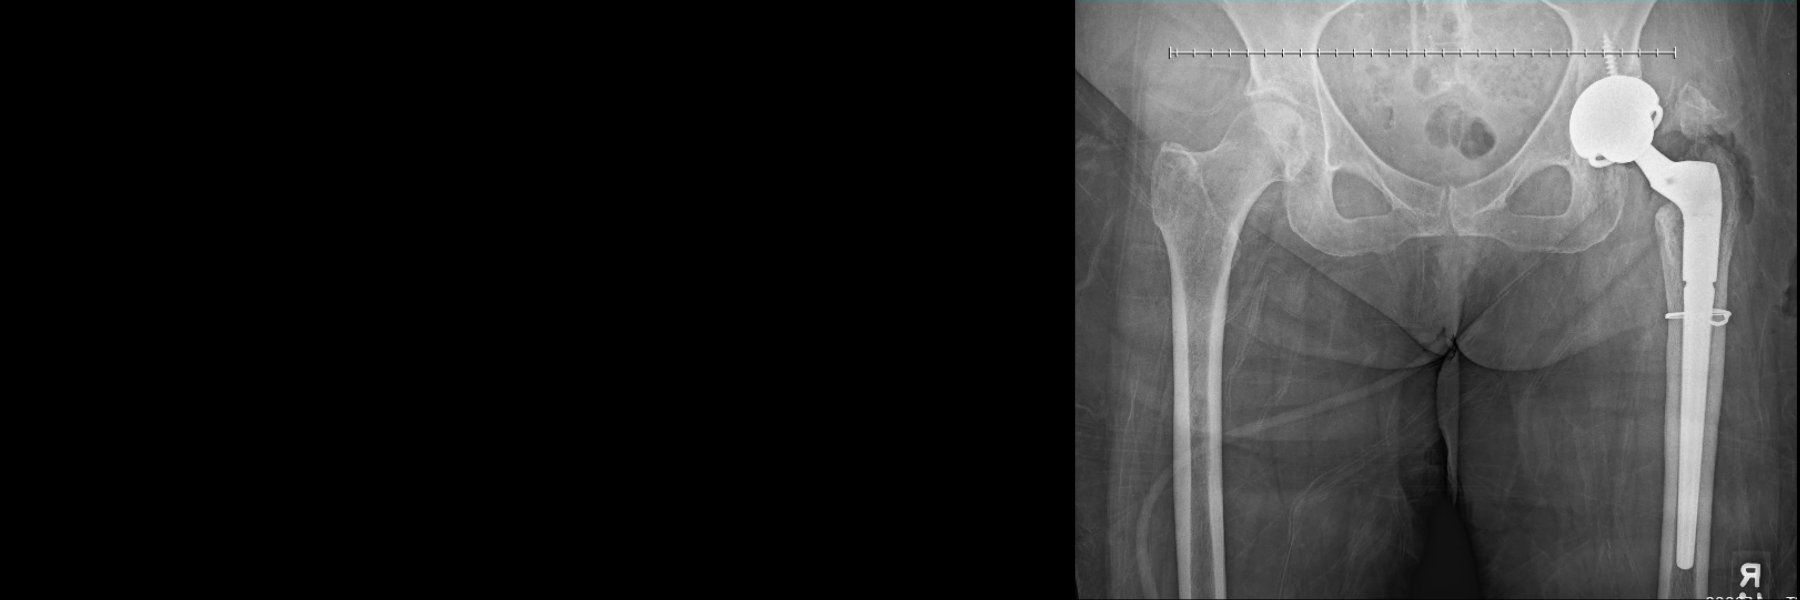

"Dr. Gladnick is not only a highly competent orthopedic surgeon but in my case, a true artist in the field of complicated revision hip replacement surgeries. My initial hip replacement (done in Reston by a Dr that has since retired) resulted in three surgeries in March/April of 2017. I was on a walker for 7 months before an X-ray showed the hip was dislocated and the...bones were floating. I had also lost a few inches in the length of the leg. I was referred to Dr. Gladnick, who took the case and reassured me that he would restore the use of the leg. He performed the surgery on Nov 1, and I was walking without any assistance within 4 weeks! Looking at the post-surgery X-rays has convinced me that Dr. Gladnick is a true artist in his ability to configure metal in a way that the floating bone could be optimally reattached where it was designed to be. He even restored the 2 inches I had lost in the length of the leg! In closing, I see Dr. Gladnick as a very unassuming, modest Dr, who has no idea how talented he really is."

The hip replacement prosthetic is a ball-and-socket articulation. The ball is made of a highly polished medical-grade ceramic, which is a very smooth and very durable material. The ceramic ball is impacted onto the trunnion of a titanium-alloy stem which has been inserted into the canal of the femur. This titanium stem is coated with a rough layer of a material called hydroxyapatite, which encourages the patient’s own bone to robustly grow onto the new stem.

On the socket side, the bearing surface is a highly cross-linked polyethylene liner, a very durable medical-grade plastic with superior wear properties. This liner is impacted into a titanium hemispherical shell, which has been inserted into the patient’s own hip socket. Like the stem, this new socket has a roughened outer surface that allows new bone to grow in, unitizing the implant to the patient’s body and providing long-lasting, durable fixation. Thus, while the implants themselves are made of titanium alloy, the final bearing surface is ceramic-on-polyethylene.